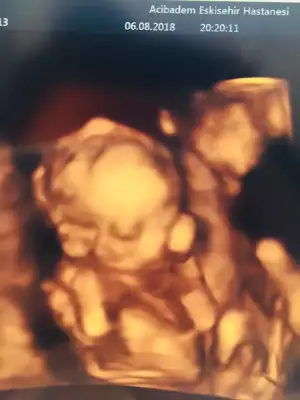

Oyyy minikkyaa bızım renklı pozlarımza bakın bugune dek bunları aldık 13haftalık biri dha 7cm orda

Bana da doktorum her gidişimde renkli görüntü verdi canım. Her defasında büyüdüğünü görmek çok güzel :)gecen bır arkadasıma da soyledım ankarada O. Ve gayet pahalı bır hastane. kadın renkli göstermemıs 17.haftada bıde dedım neden ses cıkarmıyorsun. ha şu da var benım hastaneme eşimın kuzenı gıdıyor o da daha alamamıstı onun dr.u baskası. nezaman verıyor dıye sordu bana benımkı verıyor dedım 13.haftadan buyana. dr.dan dr.a degısıyor demekkı canım![]()

evetttt yaaa resmen parmak kadarkenki halinden bebişliğe kadar olan sürecj göruyoruz nekadar şanslı bir donemdeyız kımbılır bızden sonra daha ne gelısmeler olacak şu teknolojide yerler onu pozlar hep aynı gb rahat glb ıcerde meleğinBana da doktorum her gidişimde renkli görüntü verdi canım. Her defasında büyüdüğünü görmek çok güzel :)